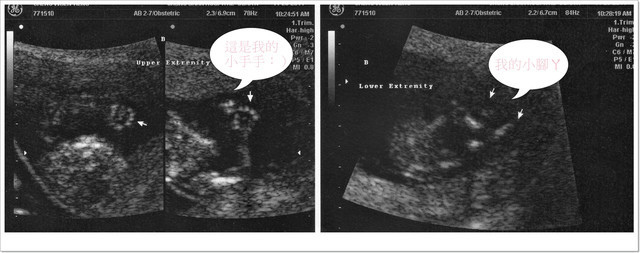

己經能移動手臂、手指及腳趾,還會微笑和大吸吮姆指哦!

A寶寶身長:5.84公分(比一般值還大) 心跳:158/分

超音波醫生非常仔細的從寶寶們的頭圍、鼻梁骨角度、手臂和大腿骨長度、腦部發育狀況、

連寶寶們的手指頭和腳指頭也都是一根根的數給我們聽哦!

大家一邊盯著螢幕一邊數著寶寶們的手指頭,1~2~3~4~5的數著真是有趣!